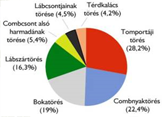

• Manuál terápia. Ízületi gyulladás és kezelése. Mágnes terápia